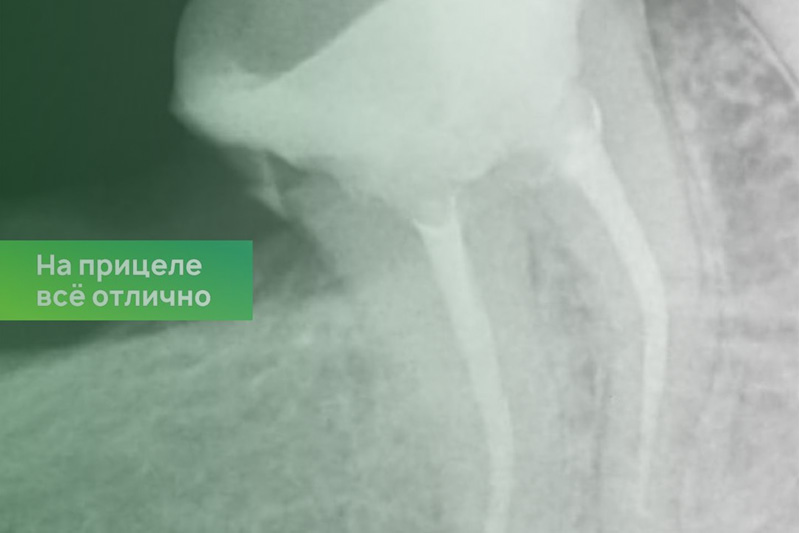

Клинический случай. Эндодонтия